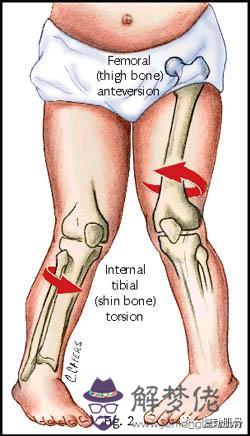

(一)股骨前傾

股骨前傾是造成3歲以上兒童步態異常最常見的原因,它是由股骨內旋引起的。到了12歲時,骨骼才會逐漸保持穩定的狀態。從12-16歲開始,隨著成年年齡的增長,這種變化會減小

(二)脛骨旋轉

這是小腿骨(脛骨)相對于大腿骨(股骨)過度向內旋轉。這也可能是由于小腿骨下部(脛骨)相對于小腿骨上部(脛骨)的內部扭曲,這是2至4歲年齡段的最常見的成因,并且該癥狀通常在8歲時消失。